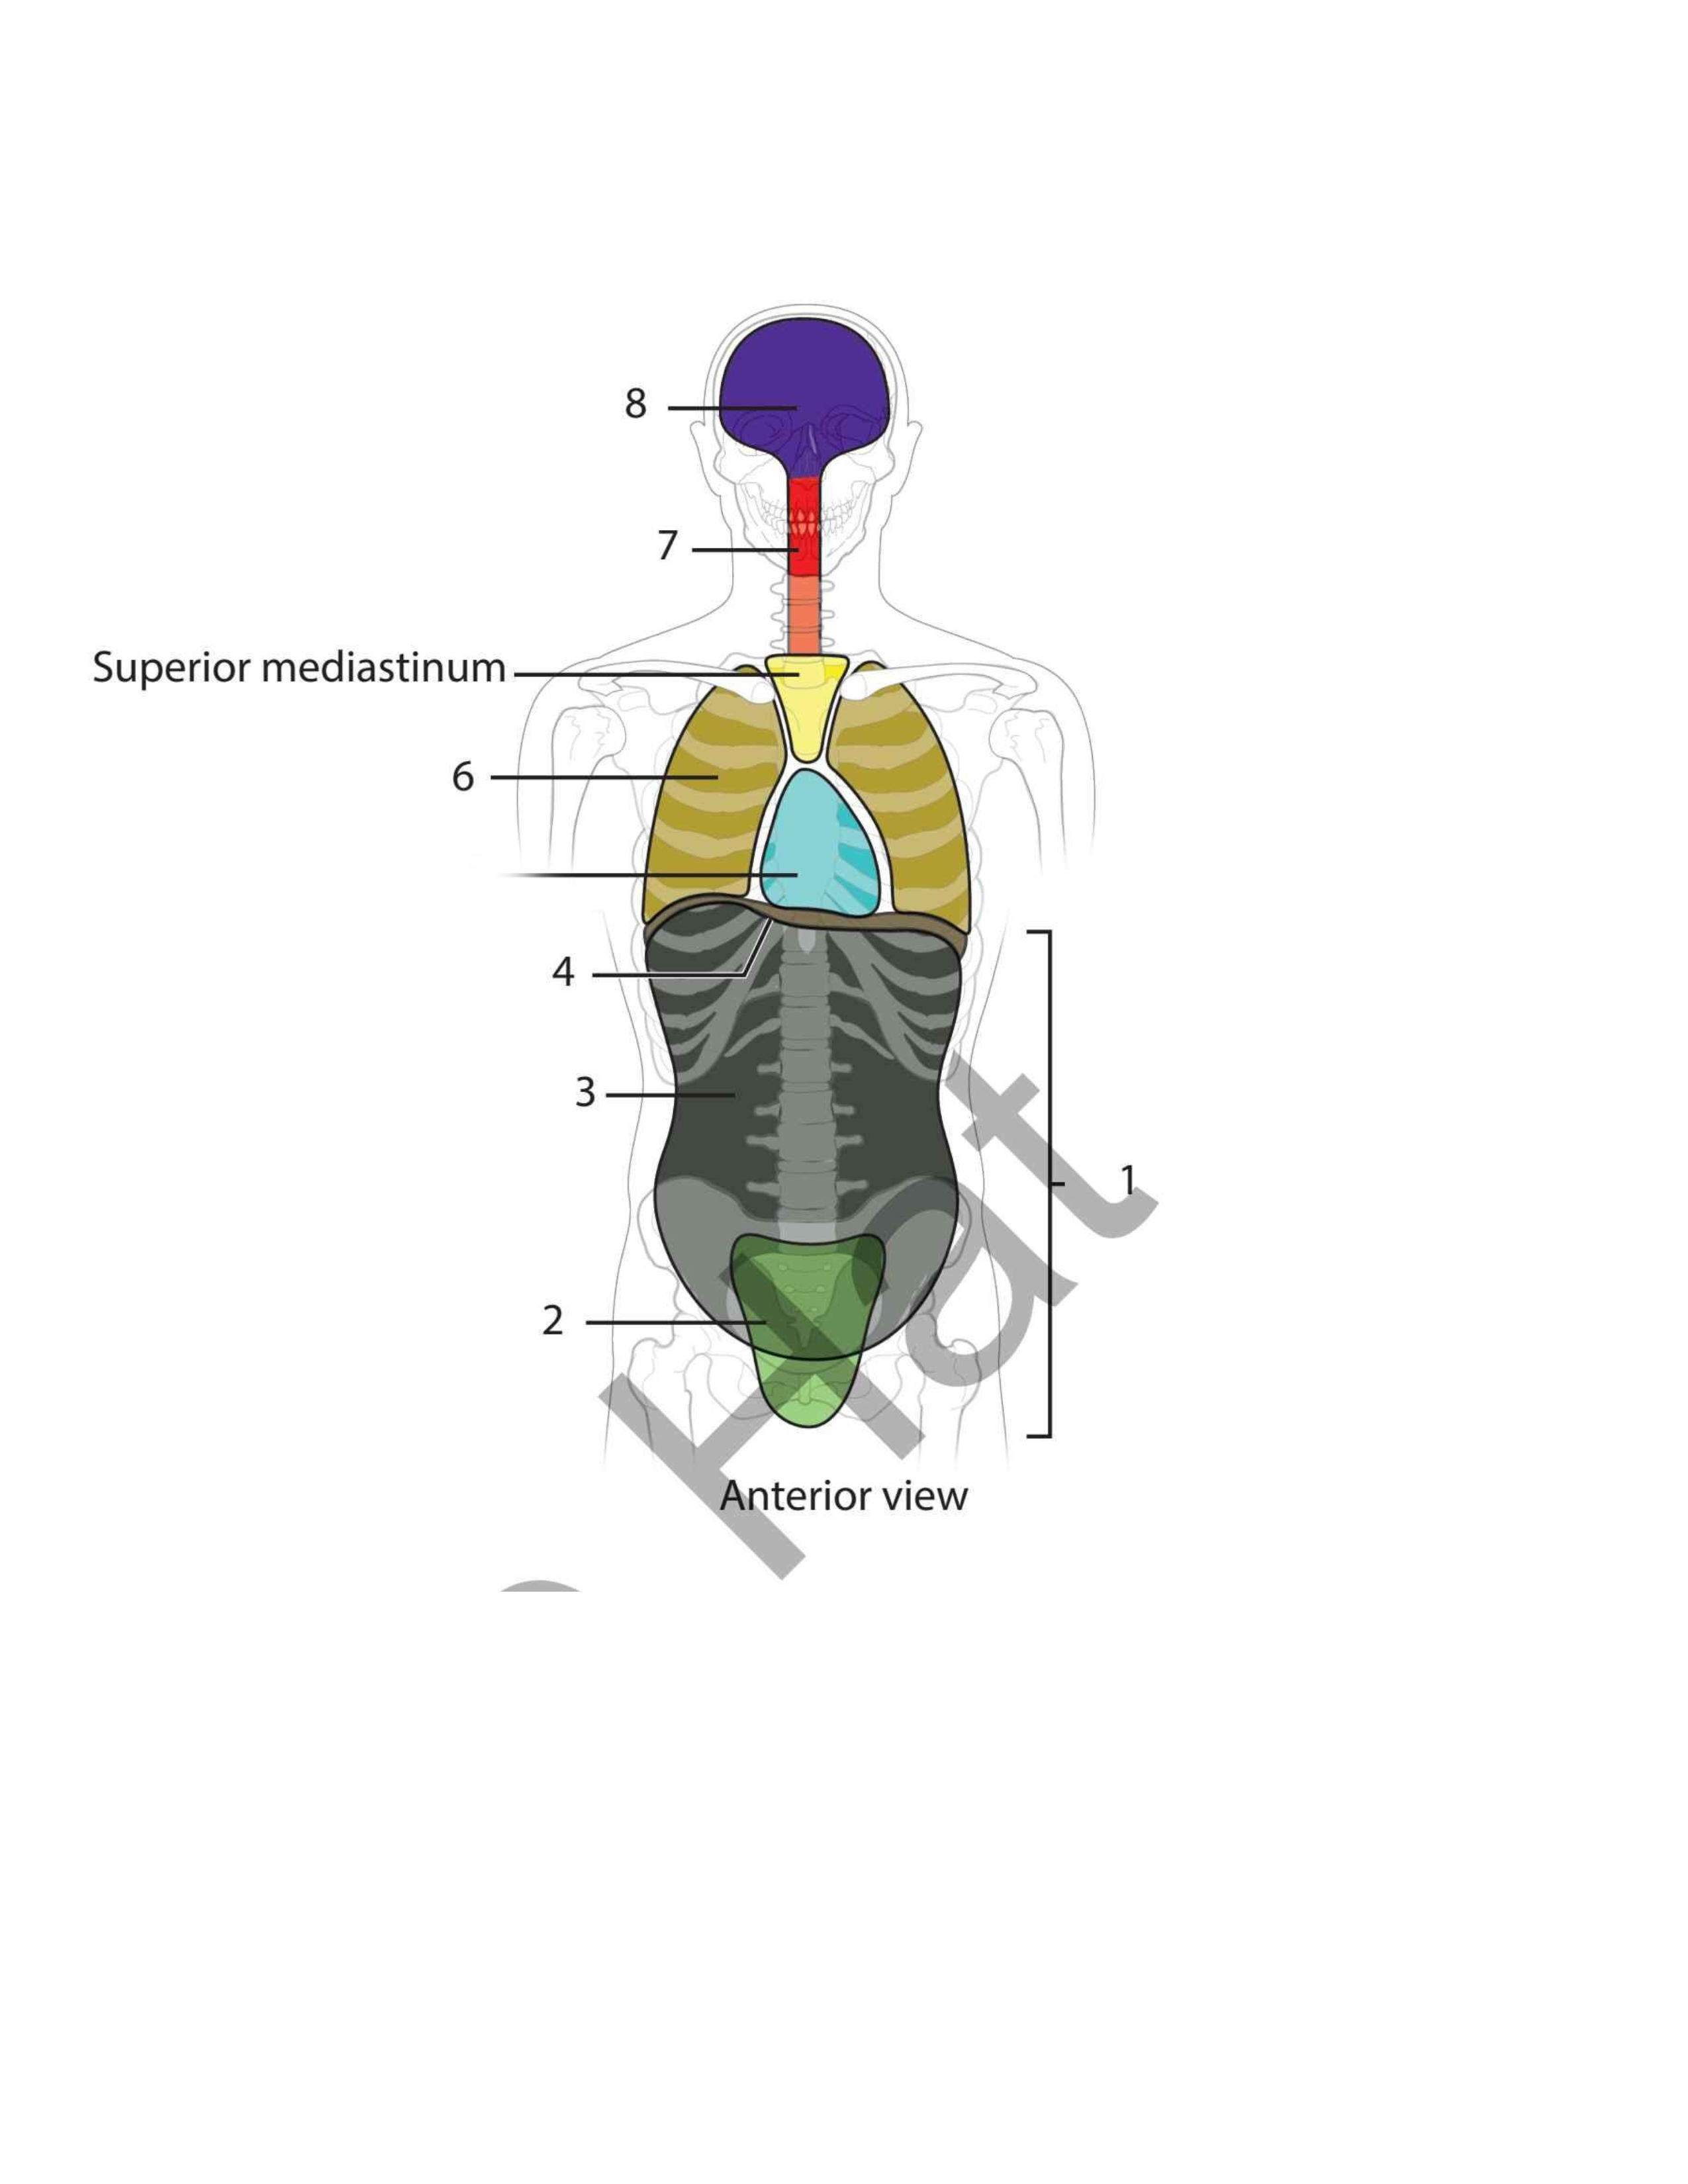

Pelvic

Abdominal

Diaphragm

Pericardial

Pleural

Vertebral

Cranial